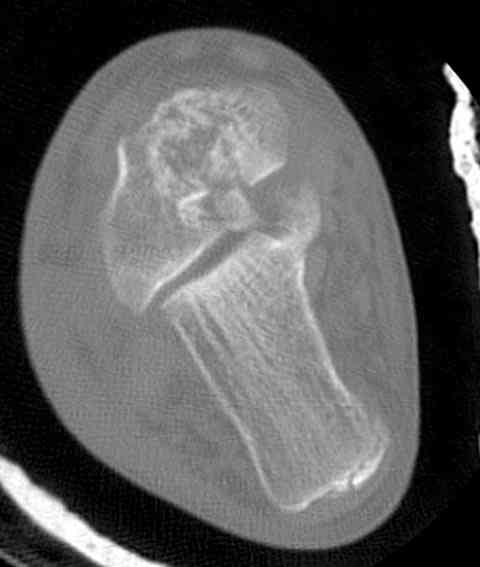

Случай с множественным оскольчатым переломом тарана оперированный из двойного доступа.

Через 2 мес.:

Через 8 мес.:

Через 14 мес.: